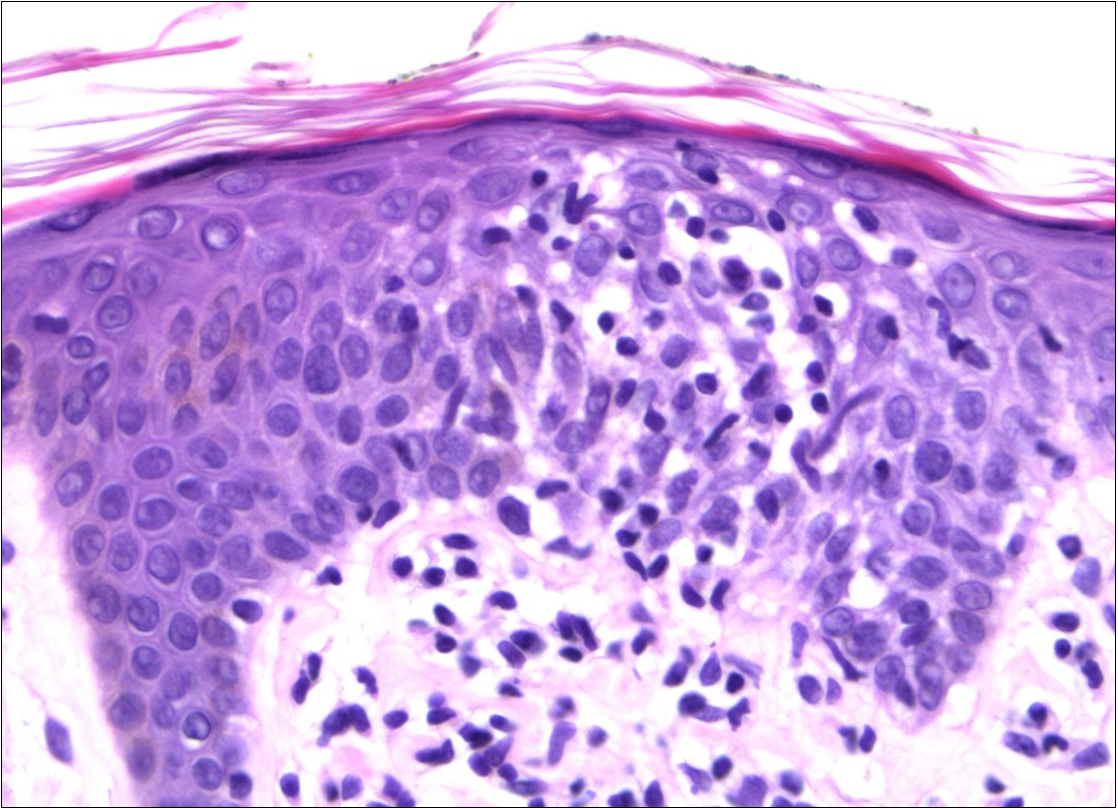

A skin biopsy revealed a dense pleomorphic lymphoid infiltrate in the superficial dermis (Figure 3) and epidermotropism. Immunohistochemistry showed a T-cell phenotype, positive for CD3, CD4, CD5 and negative for CD20.

Figure 3.The skin biopsy revealed a dense pleomorphic lymphoid infiltrate in the superficial dermis and epidermotropism (HEx40)